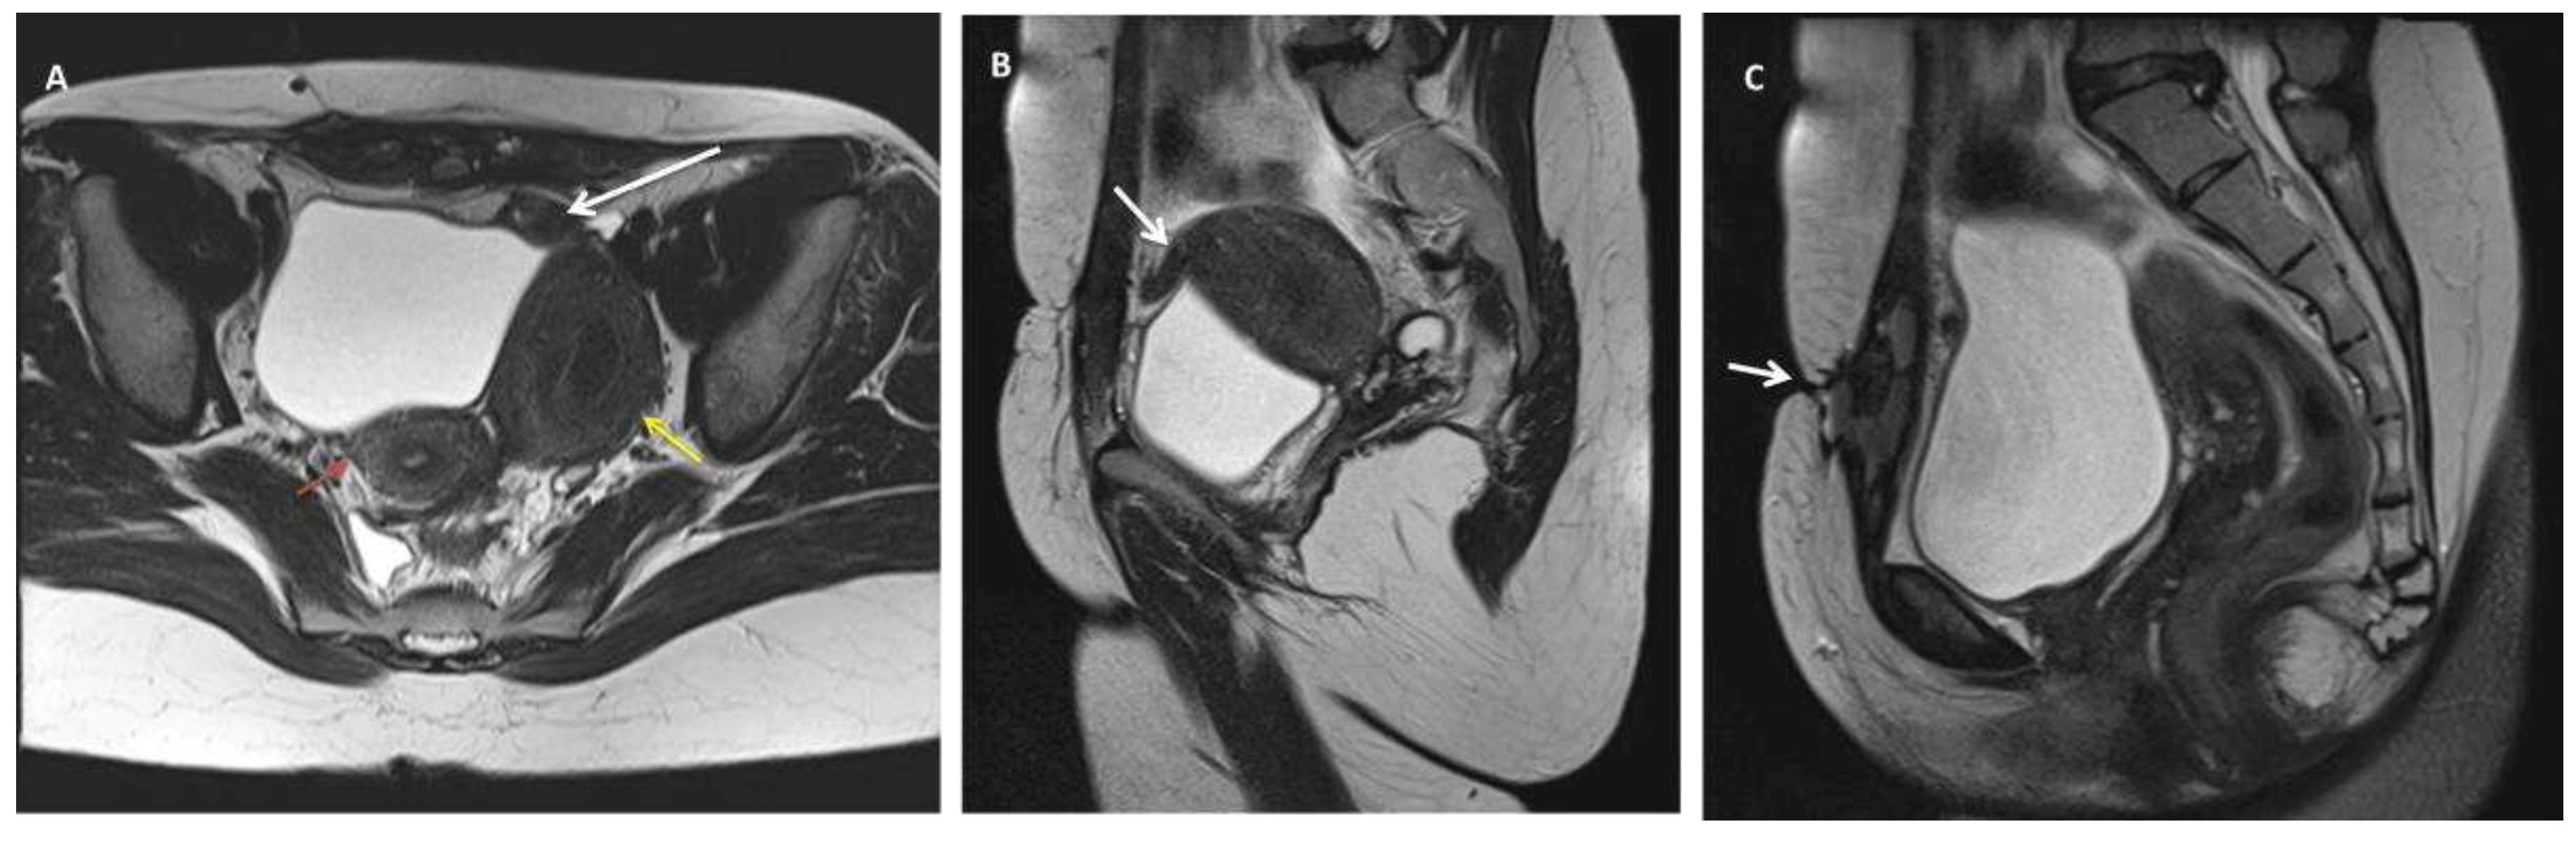

Figure 3. Pelvic MRI T2 weighted images depicting: A fistulous tract between the left hemi-uterine fundus towards the urinary bladder (without its involvement), passing anteriorly through the rectus abdominis muscles, reaching the subcutaneous tissue and the tegument in the scar area. No other endometriosis lesions were noted, and the patient was classified as #Enzian (m) P0, O0/0, B0/0, C0, FU(0), FI (abdominal wall). A) Axial view of a unicornuate right uterus (red arrow) communicating with the cervix and large non-communicating cavitary left horn (U4a) with hematometria (yellow arrow). The white arrow is pointing to a fistulous trajectory towards anteriorly and medial, confirmed in B) sagittal view (white arrow), C) that drains in the rectus abdominis muscles and subcutaneous tissue, reaching the scar tegument (arrow).